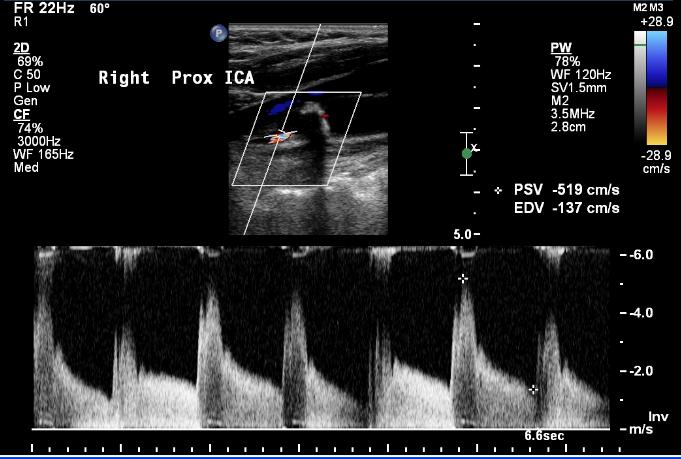

We described non-invasive imaging elsewhere. In brief – duplex, CT angiography and MRA all may play a role in pre-treatment imaging. The USPTF recommends against imaging in patients without symptoms or a bruit.